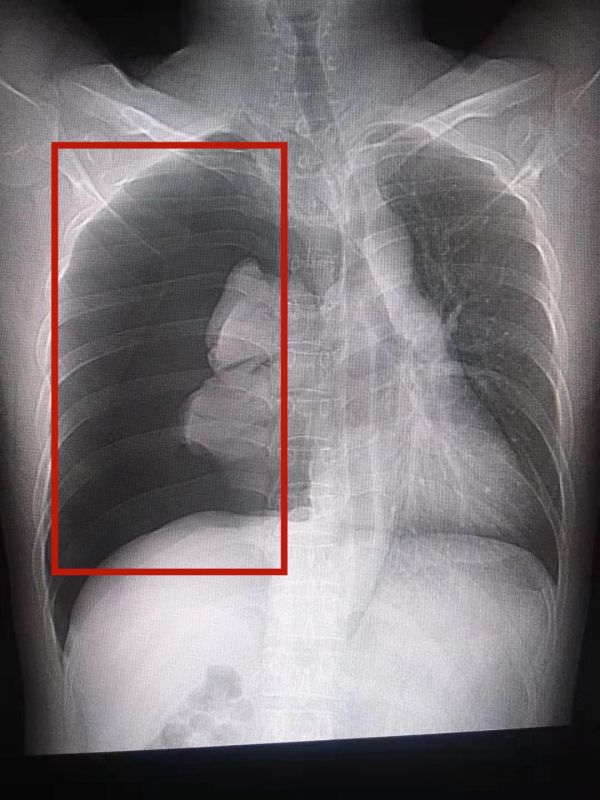

患者突发气胸,右侧肺部压缩100%。

昨晚有10年烟龄的“老烟枪”小罗晚饭后,和往常一样点燃一支烟,刚抽上两口,突然感到胸口憋气,几次深呼吸之后疼痛越发厉害。尝试几次深呼吸后,胸口疼得越发厉害。到医院检查,CT影像上发现该患者右侧肺部压缩100%,完全看不到肺纹理,且右胸呼吸音完全消失。放射科医生判断该患者患有右侧张力性气胸,可能引起呼吸循环功能严重障碍,甚至产生缺氧和休克的后果,随即为小罗安排了急诊手术。